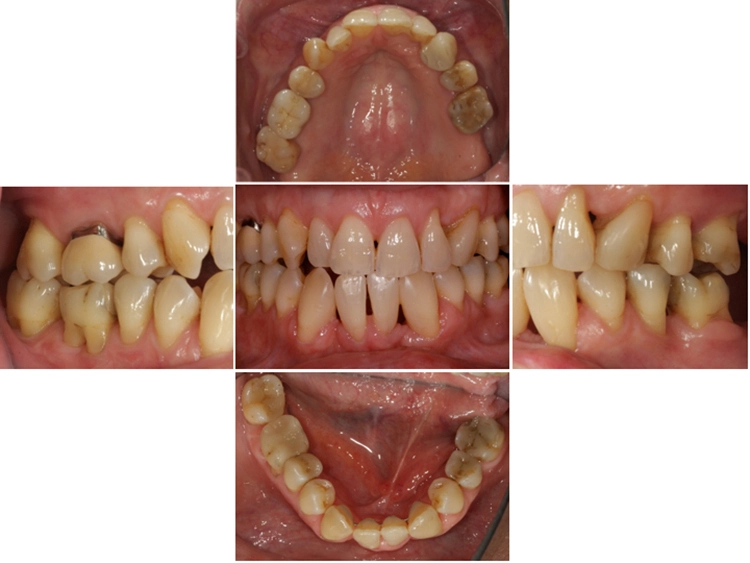

Der extraorale Befund war unauffällig. Der intraorale Befund (Abb. 2) zeigte eine lückenlose Dentition und eine verbesserungsbedürftige Mundhygiene (PI: 37%, BI: 2%) auf. Die Zähne 14 und 23 fehlten aufgrund einer Nichtanlage.

Einige Zähne waren konservierend suffizient versorgt (Abb. 3). In der Unterkieferfront bestand ein ausgeprägter Engstand mit Verschachtelung (Crowding).

Im Seitenzahnbereich bestanden an zahlreichen Zähnen Furkationsbeteiligungen. Die Zahnbeweglichkeit war an 2 Zähnen deutlich erhöht. An mehreren Zähnen lagen zudem gingivale Rezessionen vor.